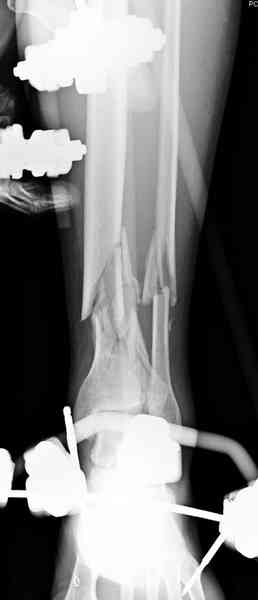

При высокоскоростных переломах редко можно встретить изолированную травму пилона, и в моей практике изолированные травмы большая редкость, поэтому, как дополнение к обсуждаемой теме, решил представить свежий, двухдневной давности случай.

Предыдущей сменой до 4:00 утра по поводу открытого перелома бедра, тибиал плато, пилон и надколенника сделана операция.

Пострадавшему 21 г., травма скоростная, после I&D с расширением раны, на бедре сделана операция ретроградным интрамедуллярным штифтом, остеосинтез с частичной резекцией надколенника и ушивание собственной связки.

На голень наружный фиксатор, рану на бедре ушили (рана была изнутри кнаружи всего 2 см). По протоколу травматических больных, до операции обследован ангиографически, (у больного дистально не смогли определить пульсацию) сосудистый хирург подтвердил проходимость на всем протяжении магистрального сосуда нижней конечности по снимкам ангиограмм.